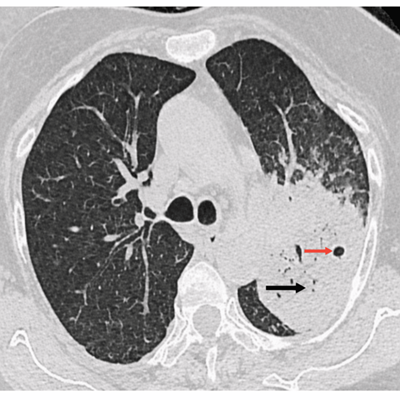

图1 胸部高分辨率CT扫描显示实变(黑色箭头)伴空洞(红色箭头)